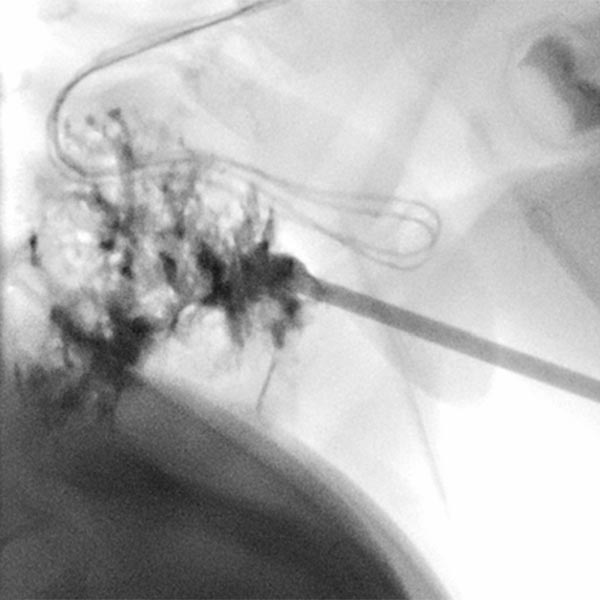

Sclerotherapy was performed in view of the rapid growth in size and recurrent painful thrombophlebitis. The contrast injection via an inserted puncture needle depicted here shows extensive contrasting of the venous malformation, thus good conditions for successful sclerotherapy.

Digital subtraction angiography after contrast injection via the same needle also shows very clearly the almost complete filling of the venous malformation from this needle position. Only small, very thin-lumen communicating veins present themselves. Therefore, a large part of the venous malformation can be sclerosed from this needle position.

In the fluoroscopic control (lateral plane) after injection of 8 ml of polidocanol foam (3%, 1 : 4 foamed in air), the entire venous malformation is filled with the non-contrasting foam. The previously contained contrast medium is almost completely displaced by the sclerosing foam. Thus there is a good chance that the lesion will be very largely closed by the procedure.